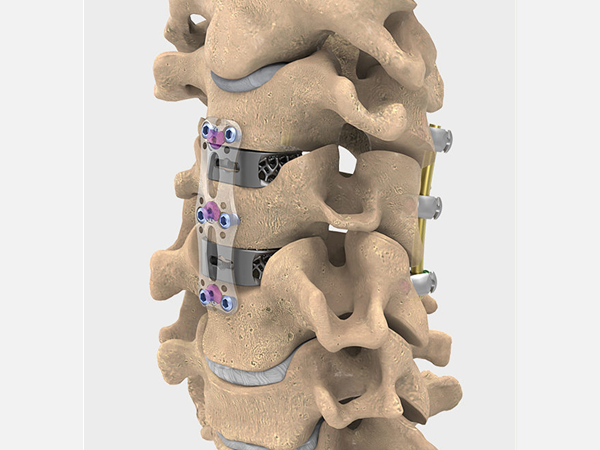

• Хирургия позвоночника

Хирургия позвоночника

2022-10-14

Changzhou Meditech Technology Co., Ltd., расположенная в научно-образовательном городке Чанчжоу, провинция Цзянсу, специализируется на производстве ортопедических имплантатов и инструментов. най